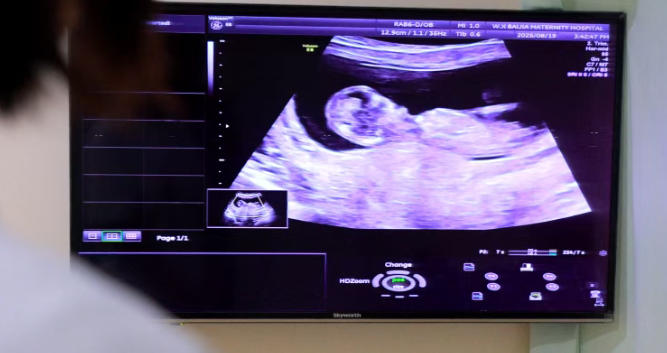

#迟发性畸形:28周后仍需警惕胎儿的发育是动态过程,孕中期四维彩超通过后,孕28-32周的迟发性畸形筛查也要重视哦。

孕中期四维超声九种严重畸形筛查,孕妈妈可点击下图一键预约